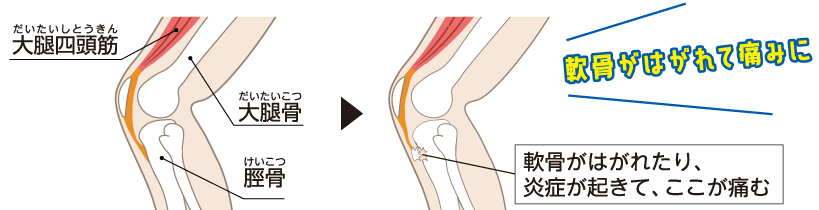

1.膝の下側が痛くなる オスグッド・シュラッター病

膝の下側に痛みが生じるのが「オスグッド・シュラッター病」です。成長途中の子どもは筋肉や腱の発達が未熟のため、膝にくっついている大腿四頭筋(もも前の筋肉)が硬いと、ジャンプやダッシュなどを繰り返すことで、脛骨(すねの骨)が引っ張られ、付着している部分がはがれたり、炎症を起こして痛くなってしまいます。